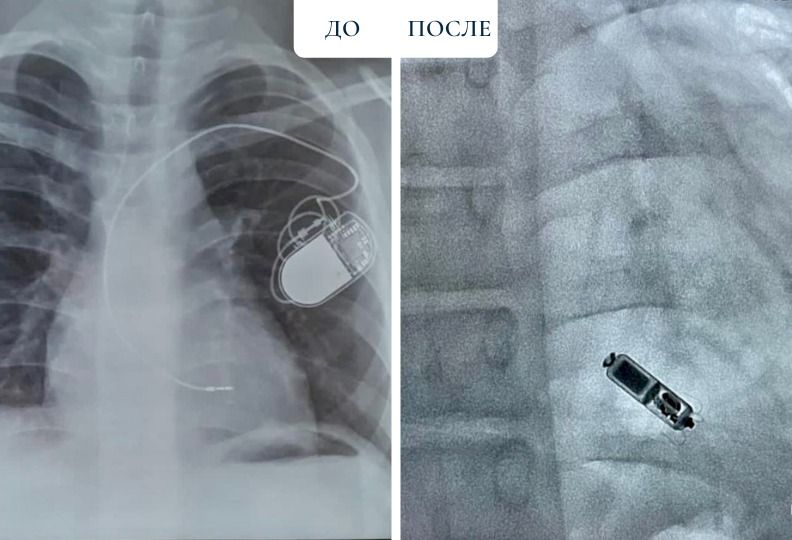

"Мы решили удалить прежнюю систему ЭКС, так как она уже не подходит пациенту. После чего мы провели имплантацию нового безэлектродного ЭКС Micra AV. Состояние пациента заметно улучшилось, а синхронизация между предсердиями и желудочками достигла 80 процентов", - рассказал заведующий отделением интервенционной аритмологии Центра Сердца Аян Абдрахманов.

Micra AV - самый маленький безэлектродный электростимулятор в мире размером с таблетку и с функцией двухкамерной стимуляции. Он устанавливается только в правом желудочке - одной камере сердца. Говоря простым языком, ЭКС Micra AV синхронизирует работу сердца.